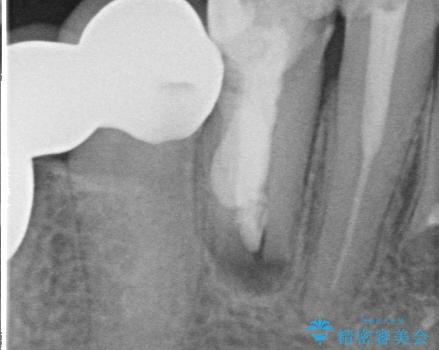

X線写真および歯周組織検査より、歯の破折 周囲骨の高度な吸収が認められました。

抜歯後、インプラントによる審美・機能改善を希望されたのでインプラント埋入に先立ち吸収した骨の再生を計画します。

歯を失う原因が虫歯や根尖病変などはなく、歯周病や歯の破折等周囲の骨を吸収する原因の場合はインプラント治療を行うに先立ち骨の造成が必要なことがあります。